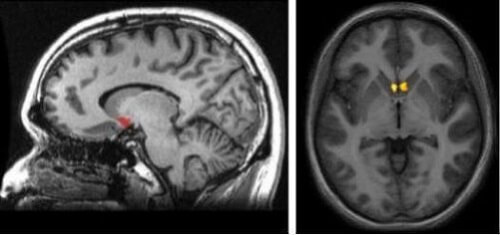

Nå kan du spørre deg selv hvor denne hjernestrukturen ligger. For å forenkle det, tenk deg det subkortiske (under cortex) området rett ved forbindelsespunktet mellom nucleus caudatus, putamen og septum. En av de viktigste aspektene ved nucleus accumbens er beliggenheten, ettersom det er en del av dopaminets vei i hjernen. Dette er den såkalte mesolimbic-banen. Det har ansvaret for å stimulere deg når hjernen din mener du er under behagelige og gledelige opplevelser.